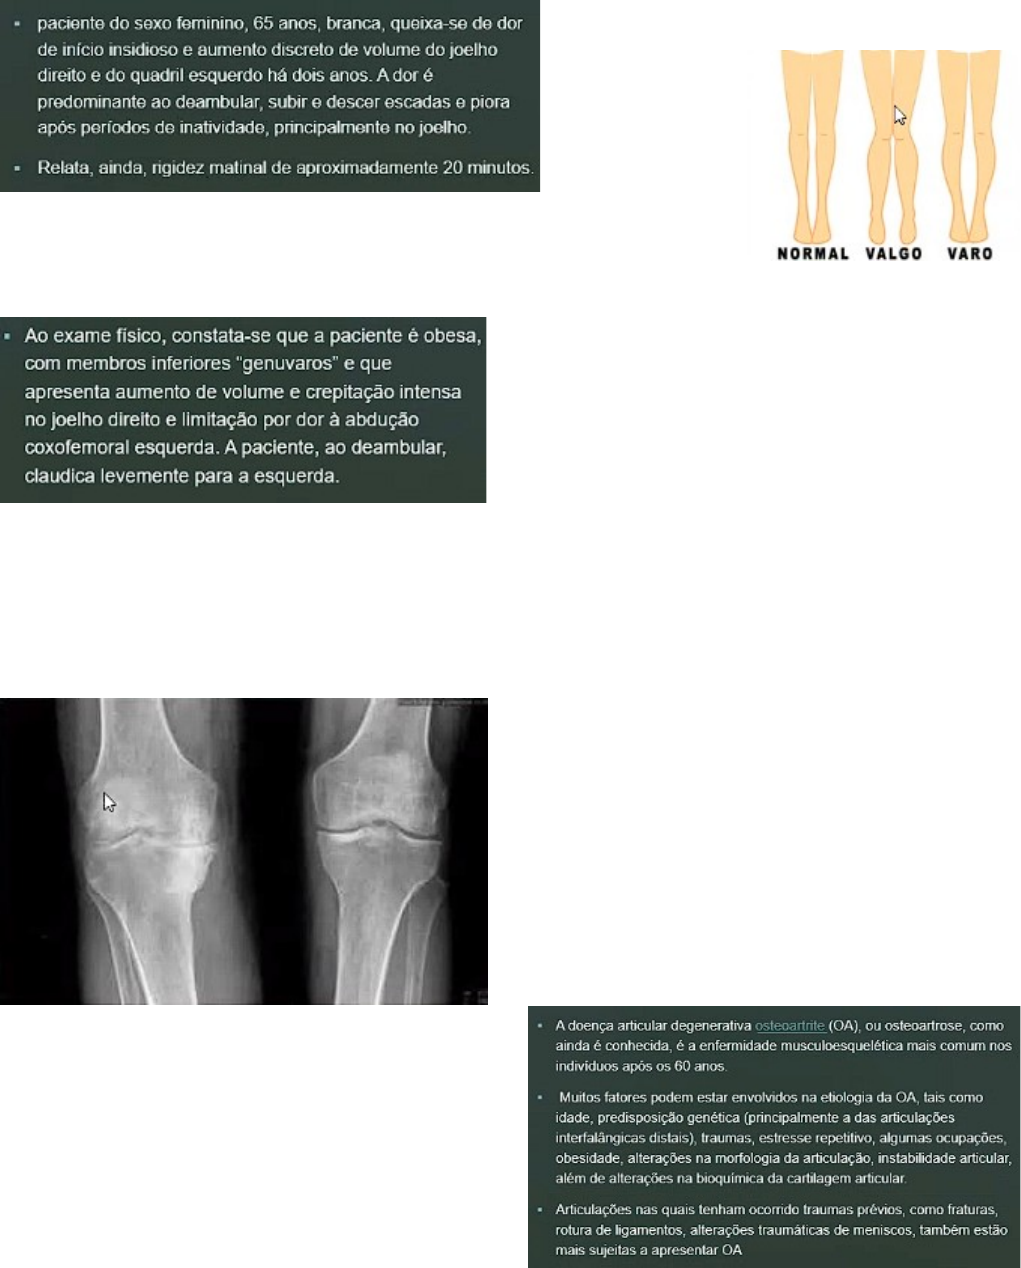

· OSTEOARTRITE: mais velha, com dor em grandes articulação (reumatoide compromete pequenas articulações e acomete próximo aos 40 anos, outras comprometem medias articulações), dor piorando após períodos de repouso, rigidez matinal, geno varo causa maior sobrecarga em um dos condilos, crepitação

Ponta de ossos: osteofitos

Diminuição do espaço articular

Neoformação óssea ressonal subcondral ou esclerose óssea